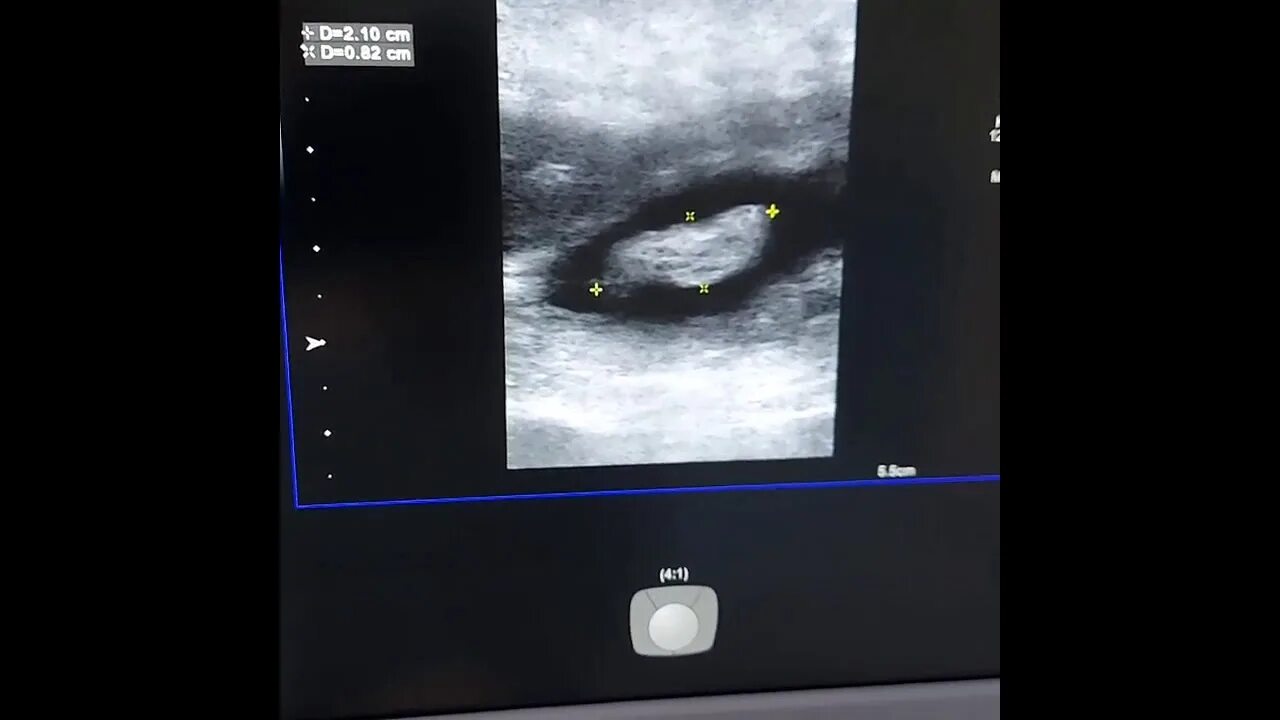

Можно вылечить полип желчного пузыря